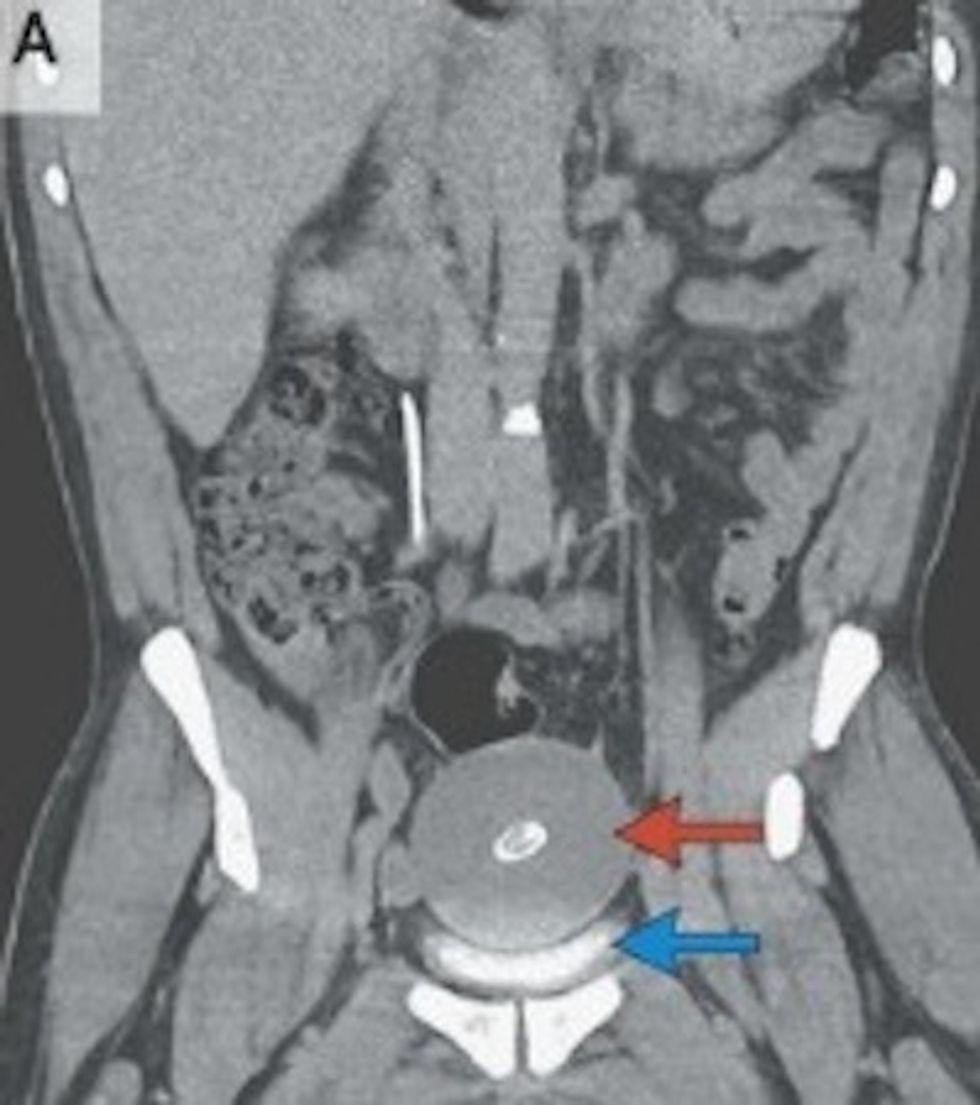

Doctors didn't find anything wrong in a physical exam or laboratory tests, but a CT scan revealed otherwise. Going into the man's pelvis with a small camera, they found what they described in the New England Journal of Medicine as a "free-floating, smooth, firm, rubbery mass."

The mass measured larger than the average chicken egg and weighed almost a half of a pound.

To further analyze the mass, Dr. Rachael Sussman from Georgetown University Hospital and Dr. Jonah Murdock with the Washington, D.C., Veterans Affairs Medical Center, dyed it green and sectioned it. They determined the mass was "predominantly acellular, laminated, fibrous tissue; centrally, the specimen contained proteinaceous material with fibrinoid necrosis, surrounded by a ring of calcification."

They believe it formed from a fatty appendage that experienced cell death, was twisted then detached, resulting in the fibrous mass.

"Such masses are often asymptomatic when they are small, but they can be large enough to cause extrinsic compression that is associated with bowel obstruction, urinary retention or (as in this patient) urinary frequency," the doctors wrote.